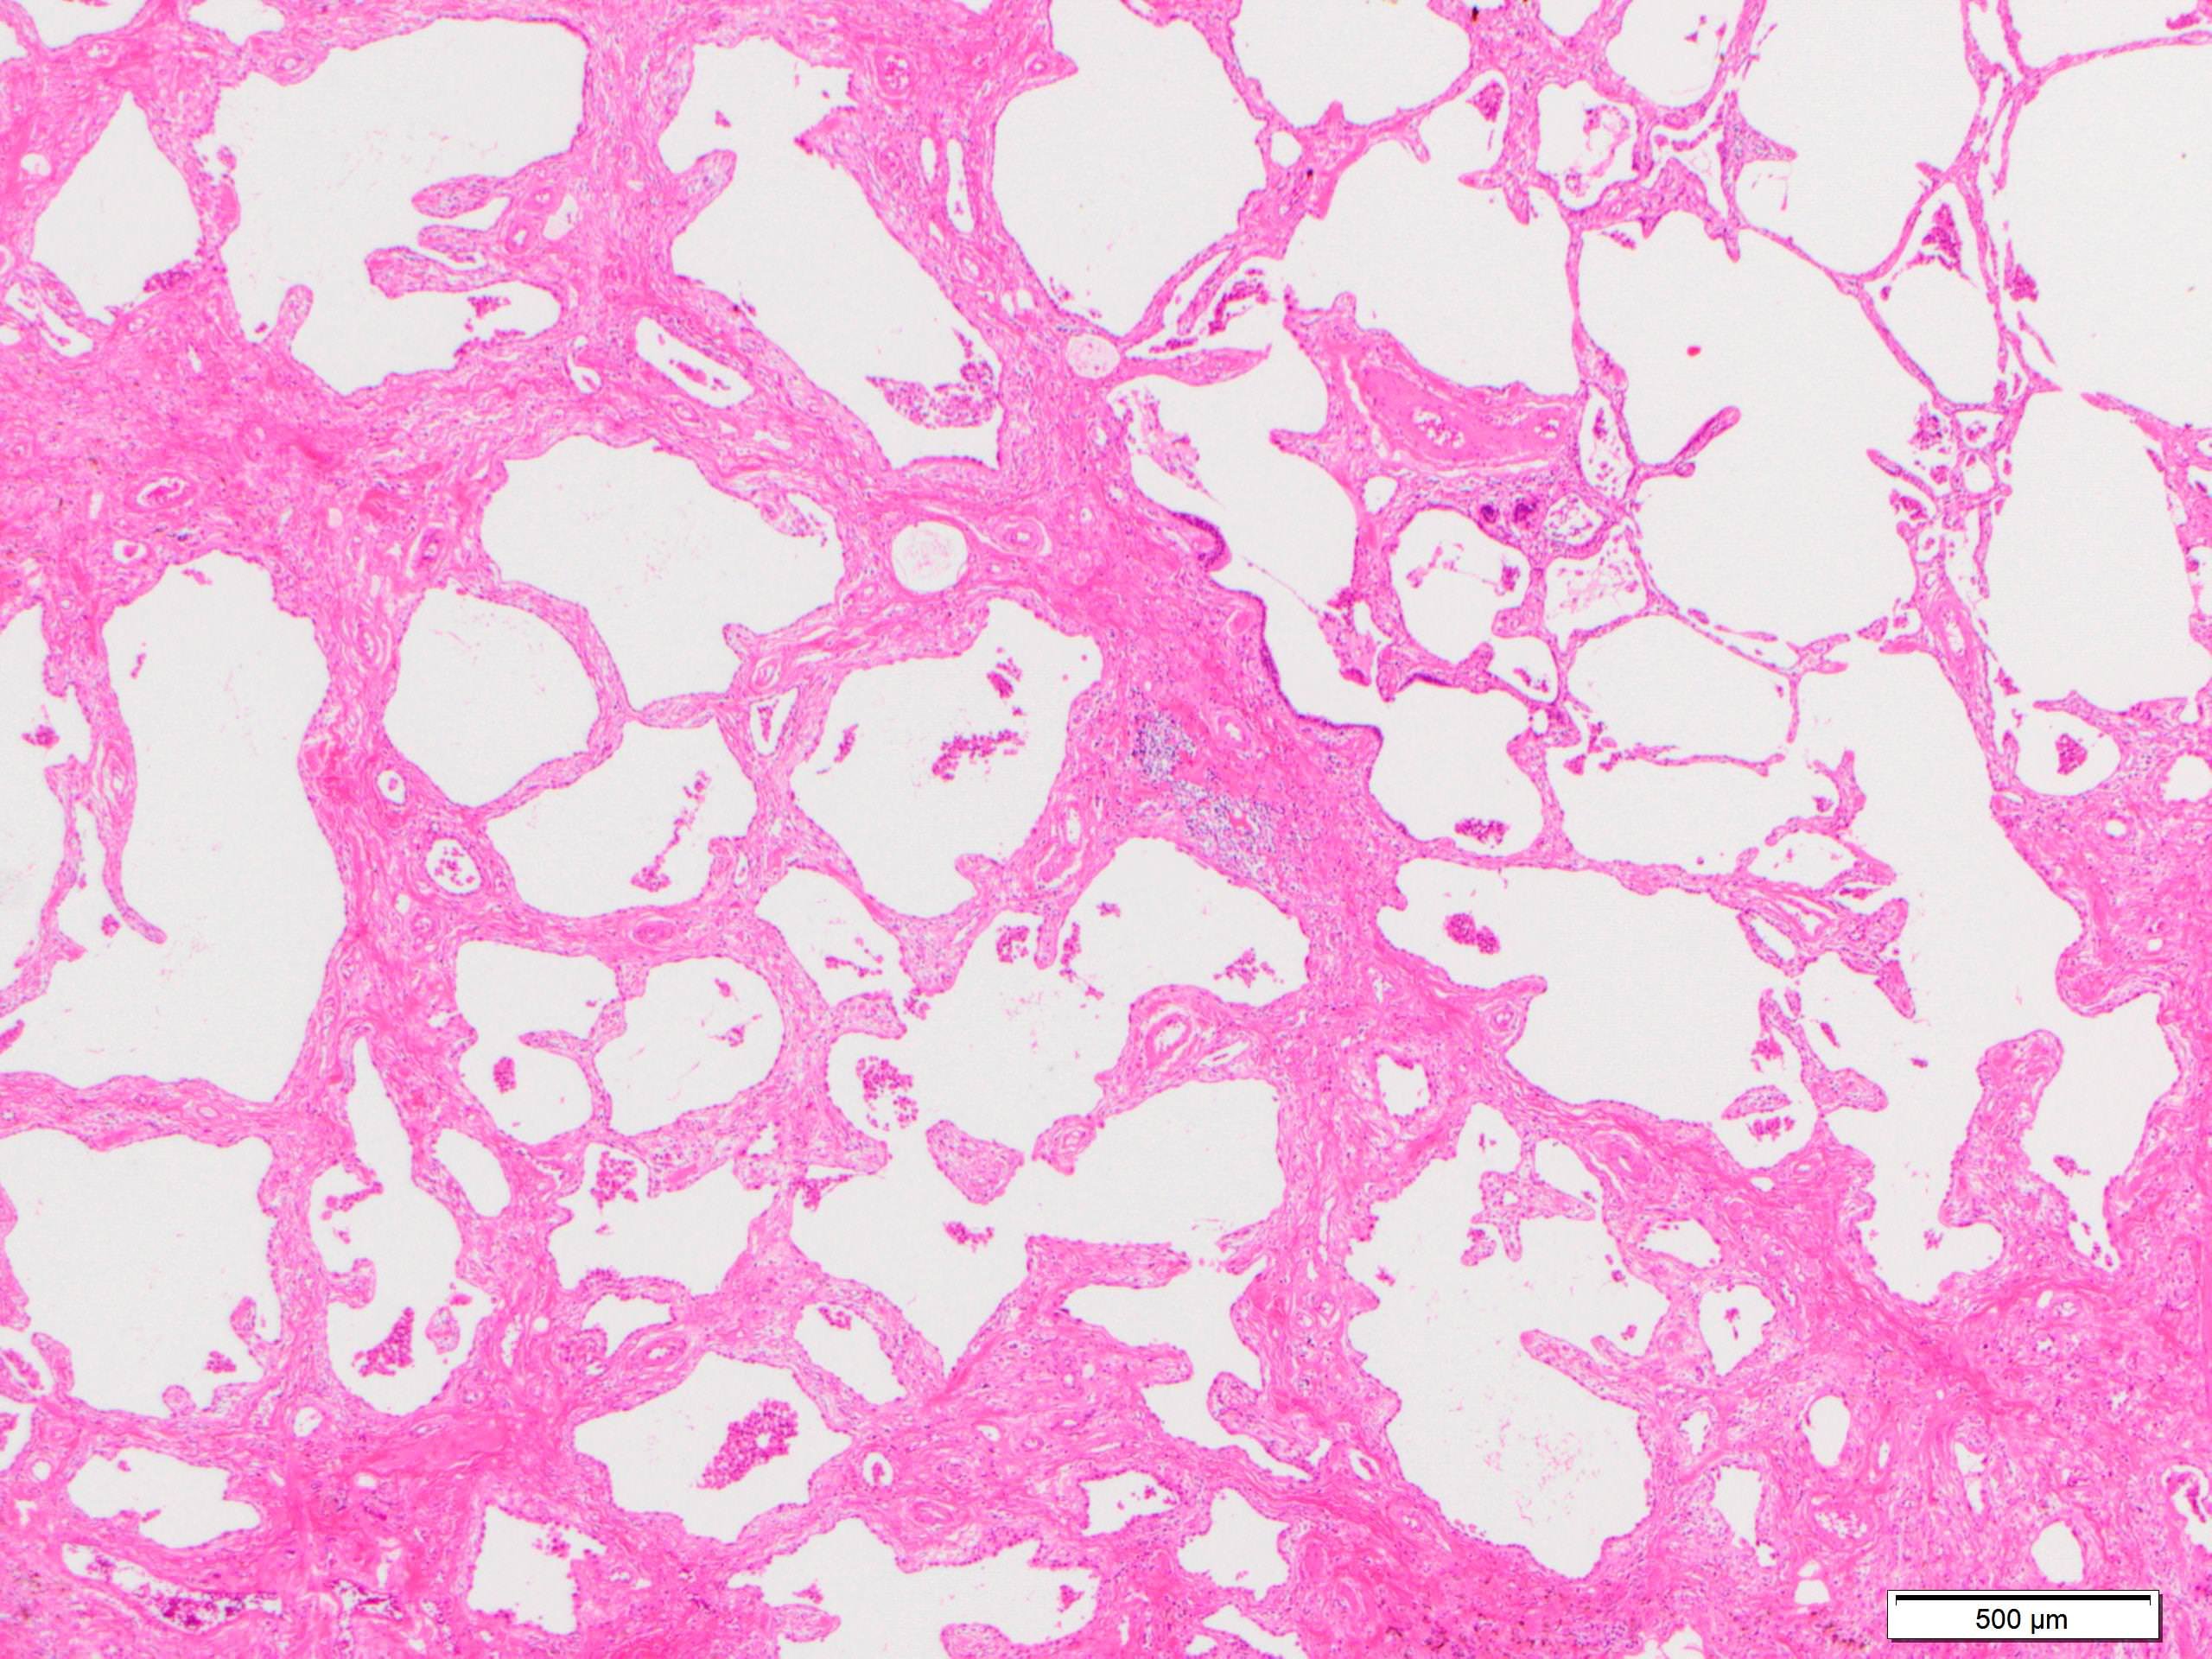

- Pertinent negative findings (Am J Respir Crit Care Med 2008;177:1338)

- UIP-like change

- Marked architectural distortion

- Dense fibrosis with smooth muscle hyperplasia or elastosis

- Fibroblastic foci

- Honeycomb change

- Hypersensitivity pneumonitis-like change

- Smoking related interstitial fibrosis (J Clin Pathol 2013;66:882)

- Alveolar hyalinized septal thickening with little cellular infiltration

- Centriacinar emphysema

- UIP-like change

Microscopic (histologic) images

Scroll to see all images.

Contributed by Akira Yoshikawa, M.D.